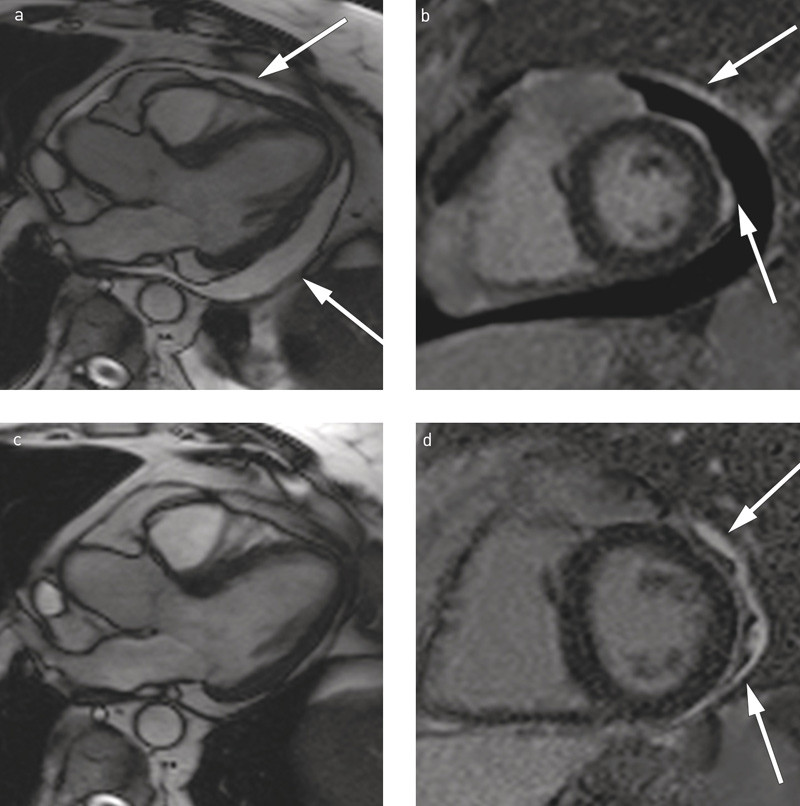

Kontrastforsterket MR-undersøkelse av hjertet (fig 2) sju dager etter symptomdebut viste perikardial fortykkelse og ujevnt kontrastopptak i perikard, mest lateralt, der det også var mest perikardvæske (15 mm brem). I tillegg påviste man et sannsynlig begrenset epikardialt kontrastopptak i myokard i samme område, som uttrykk for fibrose/nekrose. For øvrig var det normal myokardstruktur og venstre ventrikkel-ejeksjonsfraksjon (EF) > 60 %.

MR-undersøkelse tre måneder etter sykehusoppholdet viste normal venstre ventrikkel-funksjon og tilbakegang av det epikardiale opptaket i myokard, men tillegg av lateral perikardfibrose (fig 2). T1-mapping av myokard var også normal. Ingen nye kontroller ble avtalt, da pasienten også var i god form. Ett år senere hadde hun ikke vært i kontakt med spesialisthelsetjenesten.